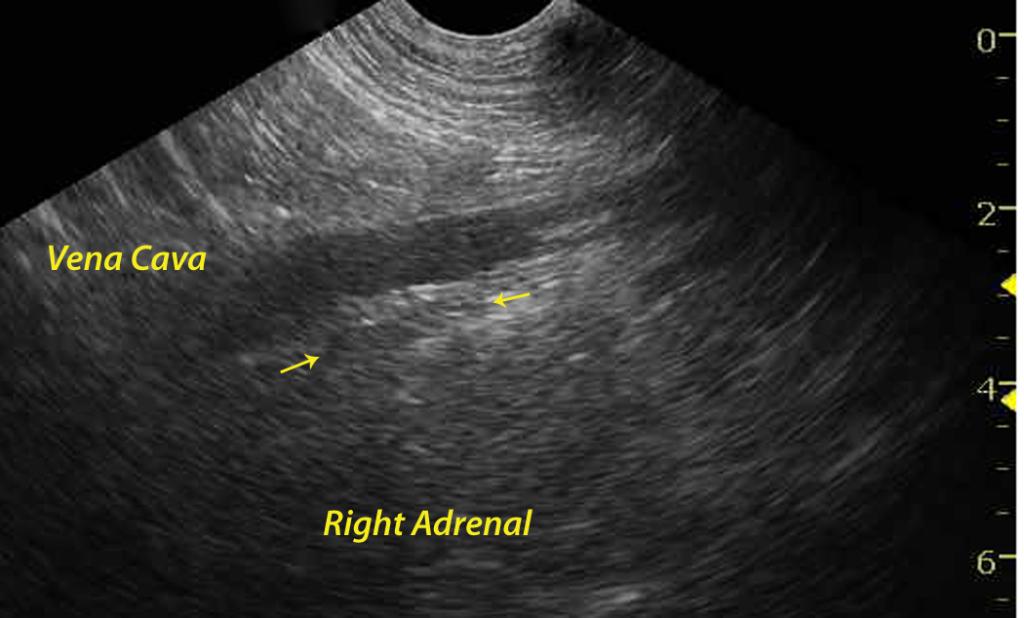

A 2-year-old FS Rottweiler dog was presented for lethargy, vomiting, and anorexia. The CBC demonstrated a leukocytosis consisting of a lymphocytosis, an eosinophilia, and a basophilia. Blood chemistry revealed azotemia, hyperphosphatemia, hyponatremia, and hyperamylasemia. The CBC and chemistry were repeated 3 days later and revealed persistence of the lymphocytosis. The serum biochemical profile revealed a decreased creatinine, hypoproteinemia, hypoalbuminemia, hyperkalemia, hypomagnesemia and hyperamylasemia.

A 2-year-old FS Rottweiler dog was presented for lethargy, vomiting, and anorexia. The CBC demonstrated a leukocytosis consisting of a lymphocytosis, an eosinophilia, and a basophilia. Blood chemistry revealed azotemia, hyperphosphatemia, hyponatremia, and hyperamylasemia. The CBC and chemistry were repeated 3 days later and revealed persistence of the lymphocytosis. The serum biochemical profile revealed a decreased creatinine, hypoproteinemia, hypoalbuminemia, hyperkalemia, hypomagnesemia and hyperamylasemia. The urinalysis showed a low specific gravity, and no bacterial growth was noted on the urine culture.